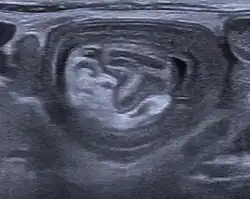

Durch eine Ultraschalluntersuchung lässt sich die Störung recht sicher feststellen, da die eingestülpten Darmteile eine zwiebelschalenartig aufgebaute Struktur (Zielscheiben- oder Target-Phänomen) bilden. Vor Einführung der Ultraschalluntersuchung wurde ein Einlauf mit Röntgenkontrastmittel unter Durchleuchtung zur Bestätigung der Diagnose und gleichzeitigen Therapie gemacht. Bei Erwachsenen kann auch die Computertomografie zur Diagnose führen.